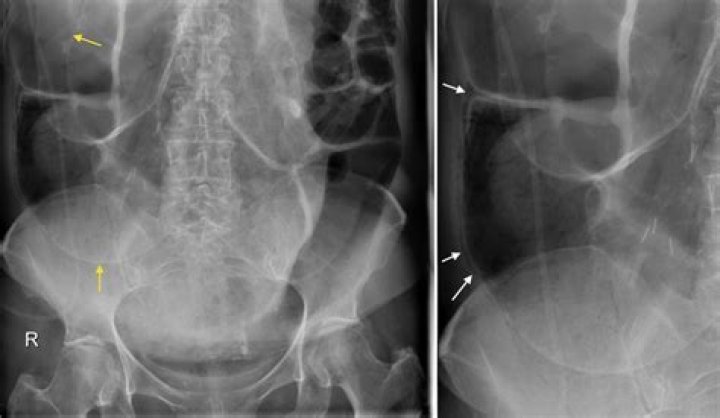

Pneumatosis intestinalis (PI), defined as gas in the bowel wall, is often first identified on abdominal radiographs or computed tomography (CT) scans. It is a radiographic finding and not a diagnosis, as the etiology varies from benign conditions to fulminant gastrointestinal disease.

Pneumatosis intestinalis is defined as the presence of gas within the wall of the gastrointestinal tract. Originally described on plain abdominal radiographs, it is an imaging sign rather than a specific diagnosis and it is associated with both benign and life-threatening clinical conditions.

Pneumatosis intestinalis is an unusual radiological finding associated with numerous pathologies from benign to life-threatening. Radiographic findings must always be interpreted in the context of the clinical presentation. A finding of pneumatosis may lead to unnecessary surgical intervention.

Pneumatosis intestinalis (PI) is defined as the presence of gas in the bowel wall [1–4]. This imaging finding is associated with numerous conditions, ranging from benign to life threatening [1–5]. The overall incidence of PI in the general population has been reported to be 0.03% based on an autopsy series [4].